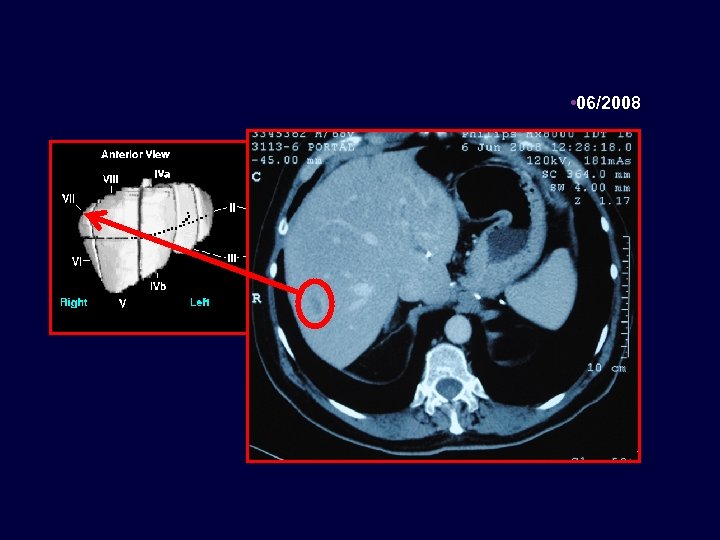

Caso clínico Paciente de 71 años con cáncer de colon estadío III en 07/2004, metastasectomía hepática en 11/2008 65 años, enfermedad coronariana, médico. Resección carcinoma de colon T 3 N 1 M 0 07/2004 Termina FOLFOX x 12 Metastasectomía hepática luego de FOLFIRI + Bevacizumab x 3 meses 03/2005 06/2008 11/2008 06/2010 - Lesiones hepáticas Quimioterapia postoperatoria con FOLFIRI + Bevacizumab - K-ras nativo

• 16/06/2010

16/06/2010 PROSTATA